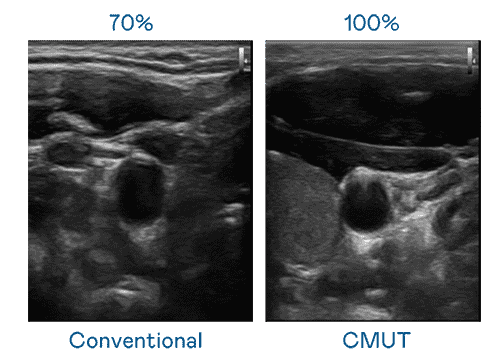

CMUT 技术是一种用电容式微机电元件来产生超音波讯号的技术。。。。与传统 PZT 压电式技术相比,,,,CMUT 频宽增加 30%,,,,更宽频的超音波讯号让影像解析度大幅提升,,是实现高影像品质医疗超音波扫描、、、促进精准医疗发展的关键技术。。

大频宽带来超清晰影像

超音波影像的解析度高低,,,首先取决于探头能发出的讯号频宽。。。红龙扑克 CMUT 可提供高清晰的超音波讯号,,,提供高频宽、、、、高灵敏度、、、影像纹理细节更高的超音波影像,,,,协助医护人员缩短影像判读时间及利用精准的医疗影像进行诊断。。。